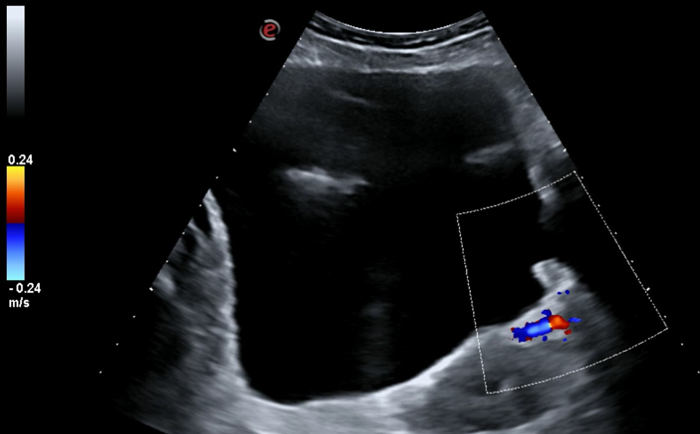

Ecografía renovescal realizada en consulta Atención Primaria: sin alteraciones salvo discreto engrosamiento en pared vesical posterior izquierda, de forma polipoide 9 x 9 mm, no captante de Doppler.

Orientación diagnóstica: sospechamos Tumor vesical.